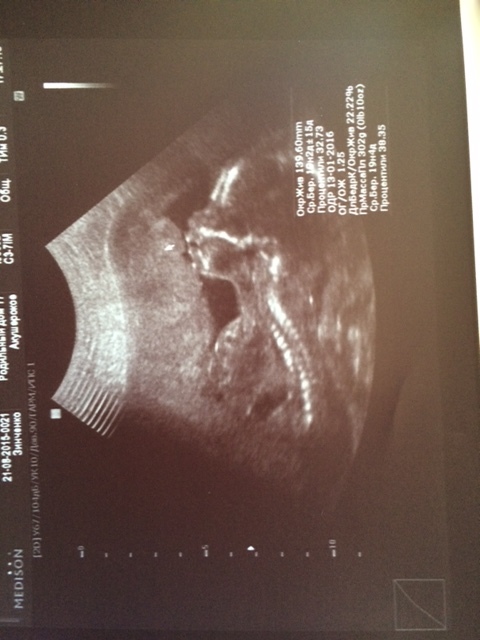

Второе фото Петрушки, как же уже хочется его расцеловать!

Встретились через экран вновь с нашим мальчиком (я до пены у рта со всеми спорила, когда узнала про беременность, что будет девочка, а не мальчик, как все предсказывали, ага..), а муж все снимал на видео. Малыш шевелил ручками, ножками, засовывал большой палец в рот, барахтался, в общем, ему там очень даже неплохо, как я поняла. Как таковых шевелений я пока не чувствую (расположение по передней стенки матки, наверху что ли, я не очень поняла).

Вес - 300 грамм, носовая кость 7,3 мм, и все остальные данные (много-много циферок) соответствуют сроку. Роддом №17, в котором я делала скрининг, сейчас закрыт на прием рожениц в связи с перегрузом, но как я поняла, в январе (ПДР на 10.01.16 г.) такой ситуации не будет. Тем не менее, решила заключать договор на роды, психологически мне так легче, знать, что точно будет наряд, что все будет доброжелательно. Сам договор заключать пока рано, о нем можно говорить после III скрининга (32-34 недели), то есть в ноябре.